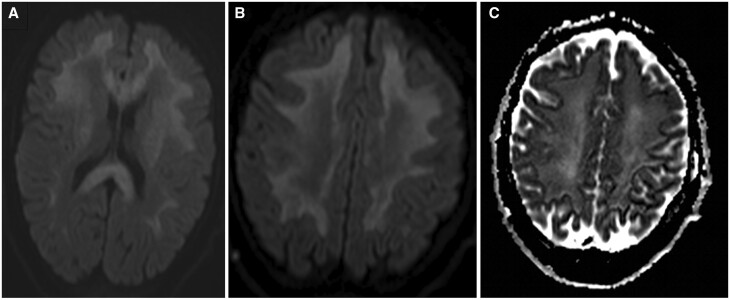

Heroin-induced leukoencephalopathy (HLE) is a rare toxic encephalopathy associated primarily with heroin inhalation, commonly referred to as "chasing the dragon." This study presents a clinical case of a 27-year-old polydrug user diagnosed with HLE during hospitalization for rapidly progressive flaccid tetraplegia and aphasia. The clinical manifestations encompassed cerebellar and bulbar dysfunction, coupled with motor impairment and altered consciousness. Based on the clinical data and MRI results, HLE was identified as the most likely cause. This article aims to provide insights into the clinical and radiological aspects of HLE, emphasizing the diagnostic significance of radiological findings. The gold standard examination for diagnosis is MRI, crucial due to the difficulties in obtaining histological confirmation for this rare condition.